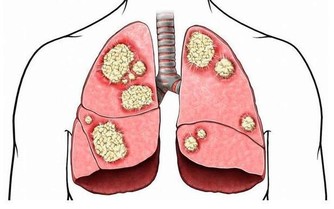

1、後外側磨損太嚴重:高弓足、O型腿

一般情況下,鞋的後外側磨損很正常,但如果磨損太嚴重就不是正常情況了。

這類人群多半是兩腿的膝關節向外分離,才會導緻小腿脛骨向內翻轉一定角度。

如果嚴重的話,就是所謂的O形腿了。

此外,高弓足也會合併有跟骨內翻,足跟外側承受較大應力,也會加重鞋的外側磨損。

1、鞋底外側磨損 可能有關節炎隱患

正常鞋子的磨損重心在腳跟中間,並可從鞋跟外側看出約4度的傾斜,但如果傾斜大於4度,就說明腳跟外側受力過多,這種情況通常由於高弓足讓體重過多傾向於腳外側,造成鞋外側磨損突出。這種走路方式容易導致關節扭傷和損傷,長期的受力不均也會導致膝蓋外軟骨的磨損,引發關節炎。這種方式也會給髖骨施壓,導致坐立時骨骼的長久疼痛。

【點評】鞋底外側的磨損可能與兩腿的膝關節向內收的走路方式有關。這種走路方式容易導致關節甚至損傷,長期受力不均還可能導致膝蓋外軟骨磨損,引發關節炎。值得注意的是,如果孩子從小就習慣這種走路方式,可能會給髖骨施壓,不利骨骼健康。